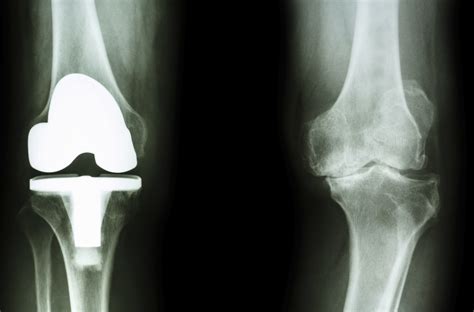

• Total Joint Replacement: This involves replacing the entire joint with an artificial implant. Common examples include total hip replacement and total knee replacement.

• Partial Joint Replacement: In this procedure, only the damaged portion of the joint is replaced. For example, a partial knee replacement may be performed if only one compartment of the knee is affected.

• Surgery: The surgical procedure involves making an incision to access the joint, removing the damaged bone and cartilage, and replacing it with an artificial implant. The type of implant used depends on the specific joint and the extent of the damage.